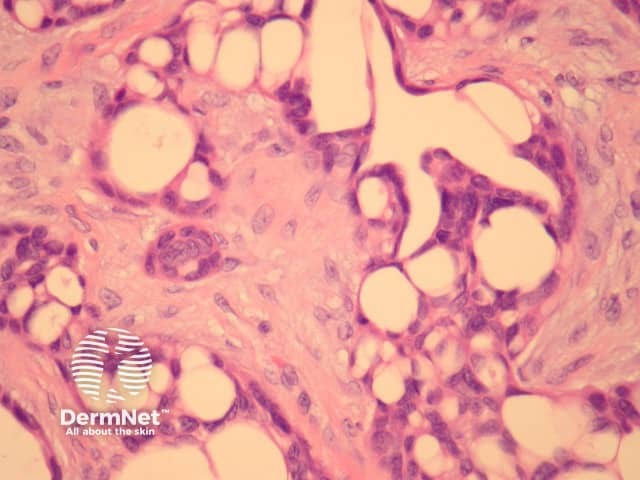

The tumour forms tubular and tubulo-papillary structures (figures 2, 3). The ducts are mainly lined by 2 or more cell layers of bland epithelial cells with limited mitotic activity. Some cells have an eosinophilic cytoplasm.

Figure 3